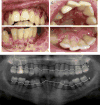

We present a 17-year old girl with DOCK-8 deficiency, severe untreated oral HSV-1 infection and associated aggressive periodontitis. DOCK-8 deficiency is a primary immunodeficiency, caused by biallelicloss-of-function mutations in the DOCK8 gene, often leading to severe viral and fungal mucocutaneous infections. Nevertheless, to date DOCK8 has not been associated with severe periodontitis and inflammatory bone loss around teeth. Understanding whether DOCK8 deficiency or severe HSV-1 infection underlies susceptibility to periodontitis is central to this case and may provide insights into susceptibility factors for periodontitis in the general population. Our clinical and microbiological data suggest that severe HSV-1 infection is the driver of periodontal inflammation in this case.